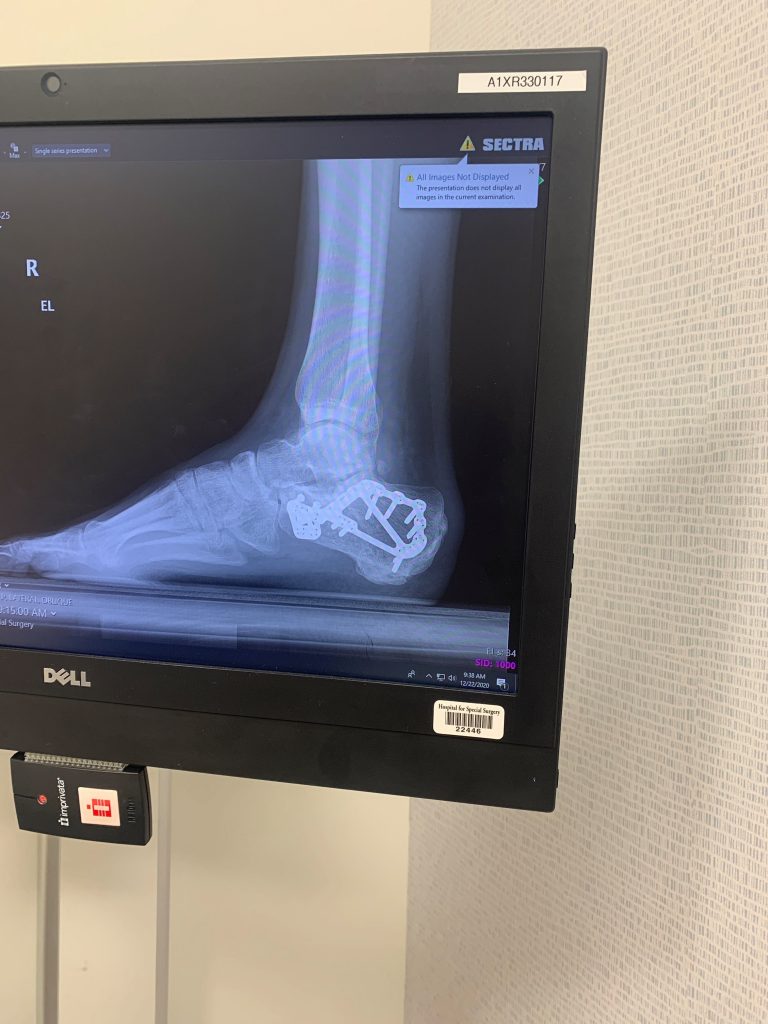

I’m a young New York City fireman. I was 29 when I had my accident (fractured calcaneus). It was a personal jet ski accident when I made such a force of contact with the jet ski that I fractured my whole foot. As a result, I received a plate and 14 screws I believe.